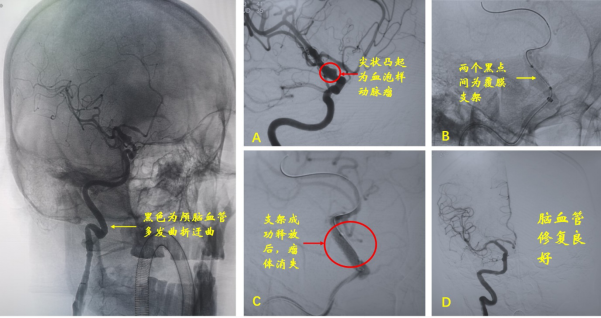

来不及迟疑,团队成员乃比江医师与胸痛中心导管室沟通后,行全脑血管造影检查,结果提示右侧颈内动脉床突上段前壁凸起,结合凸起部位、形态等特点,罗岗判断患者所患为动脉瘤中非常凶险的一种类型——血泡样动脉瘤。

经过团队讨论后,罗岗认为微创覆膜支架对于该类动脉瘤瘤体的隔绝是最佳治疗方案,虽然其支架本身比较僵硬,路径迂曲时可能存在输送失败,并且可能覆盖分支导致偏瘫或者支架内漏导致再出血等风险,但是基于不同的技术组合及合适的支架大小,可以大大降低这些风险,而提高手术成功率。

在团队的密切配合下,历经2小时手术顺利完成。术后患者恢复良好,无并发症发生。出院时患者丈夫对罗岗说:“感谢您给了我爱人第二次生命。”